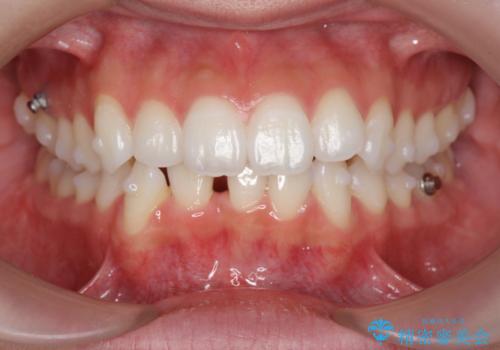

通常口元の突出感の改善を行うには小臼歯の4本抜歯が検討されますが、歯のガタ付きが下顎前歯に限定していることから

下顎前歯を1本だけ抜去を行い、上顎の歯は可及的にマイクロインプラントを用いた後方移動を行い口元の印象の改善を計画することとなりました。

マイクロインプラントを用いてしっかりと後方移動を行ったことで前歯の角度は改善され、口元もすっきりと仕上げることができました。